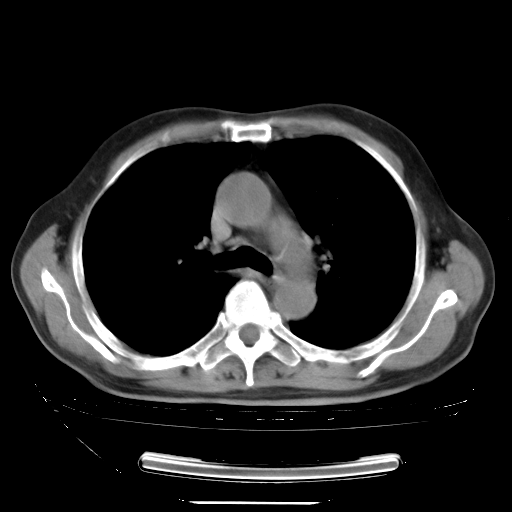

今天复查肺部CT,发现双肺广泛磨玻璃样改变。所以我把3月19日和5月9日相隔50天的肺部CT上传。请大家会诊。

5月9日肺部CT(在4月27日齐鲁医院肺部CT描述部分肺组织磨玻璃样改变,12天后肺组织广泛磨玻璃样改变)

2009年5月9日肺部CT

大致读了系列胸部CT:纵隔窗无明显异常,肺窗:从4、27至今:主要是双肺中下野外带可见毛玻璃样改变,目前处于急性肺泡炎阶段,至于原因考虑1、结替组织或胶原血管性疾病所致?2、恶性疾病如恶组在肺部所致的表现或细支气管肺泡癌?3、药物或其它原因如肺蛋白沉着症所致肺泡炎目前不太可能?总之,明天就去请我院的呼吸科、感染科、血液科和临免专家会诊哈。